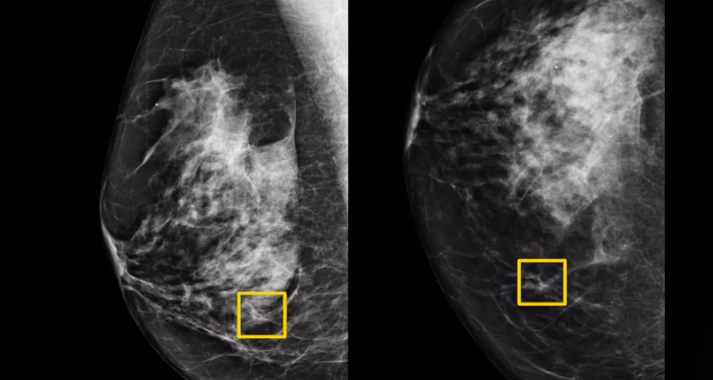

Nature子刊:1篇论文,191个乳腺癌潜在靶点

1月7日,发表在Nature Genetics上的一项关于乳腺癌遗传学的大型国际研究发现,超过350个DNA“错误”会增加个体患乳腺癌的风险,这些错误可能影响多达190个基因[1]。来自全球450...